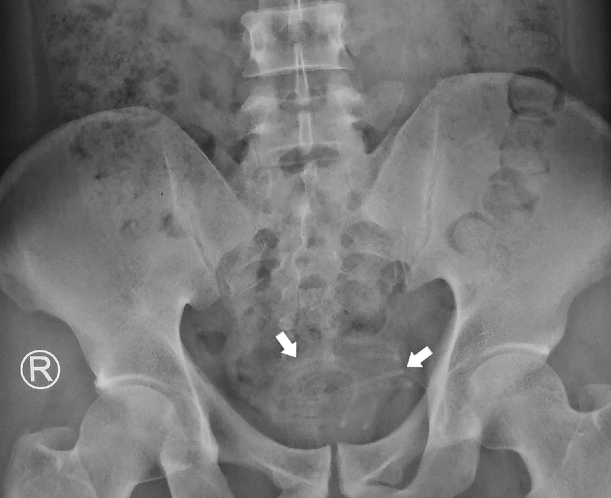

Chụp X-quang vùng chậu cho thấy một bóng mờ hóa ra là một sợi dây.

Theo các bác sĩ, sợi dây được cuộn lại và may mắn là không dính vào thành bàng quang, và việc lấy ra được thực hiện bằng kẹp nắm.

Dây tai nghe được phát hiện dày 2-3mm và chiều dài 80cm.

Bệnh nhân đã nhét dây tai nghe chiều dài 80 cm và đường kính 2-3 mm vào niệu đạo lúc 'tự sướng'.